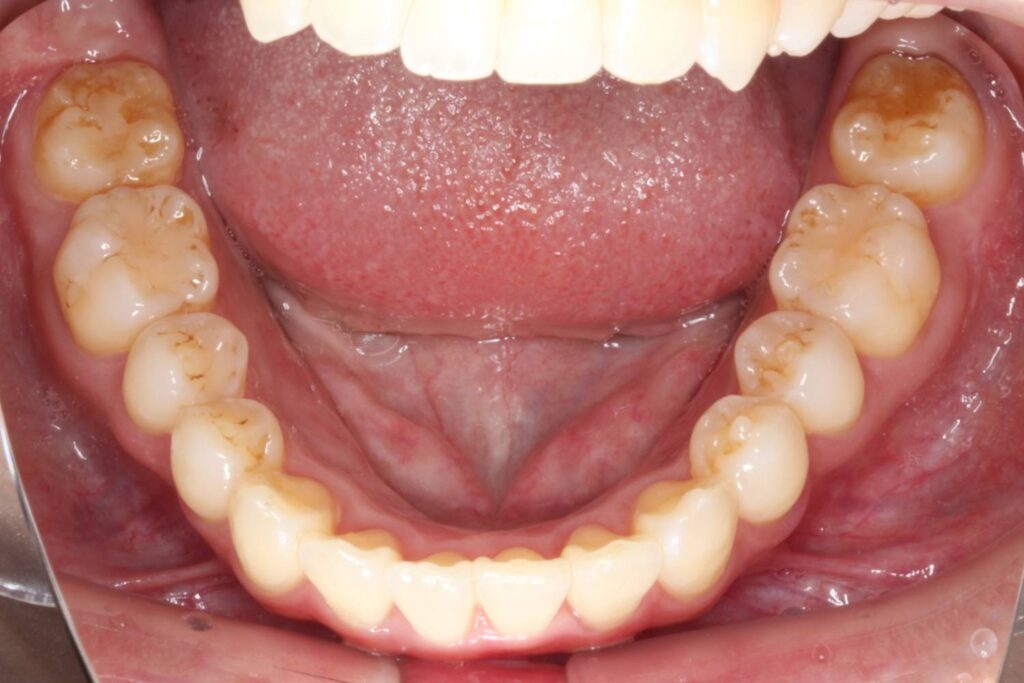

After

治療後は上顎の前歯が引っ込み、歯のがたつきも改善しています。

そうすることで、見た目だけではなく、前歯でものが噛み切りやすい機能的な歯並びが達成されました。

上顎の歯のみを抜歯していますが、噛み合わせのバランスには全く問題ありません。